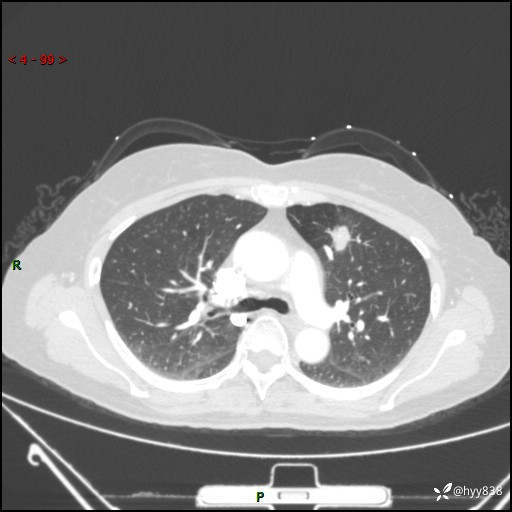

54岁/女,发现肺占位1天。观其形态和强化,术前我信心十足,术后我---结果公布~

【患者信息】:54岁/女

【主诉】:发现肺占位1天

【现病史及既往史】:患者2023.10.23体检发现肺占位:,2023.10.23当地区中心卫生院胸腹部CT:1.左肺上叶结节,考虑为占位可能;2.肝脏小囊肿灶;3.子宫左侧附件区畸胎瘤;无咳嗽咳痰,无恶心呕吐,无发热,无胸闷胸痛等不适;现患者为求进一步诊治来我院,门诊以“肺占位”收入我科。 患者自起病以来,精神饮食睡眠一般,大小便正常,体力体重无明显下降。

【检查】:胸部CT增强(外院平扫)